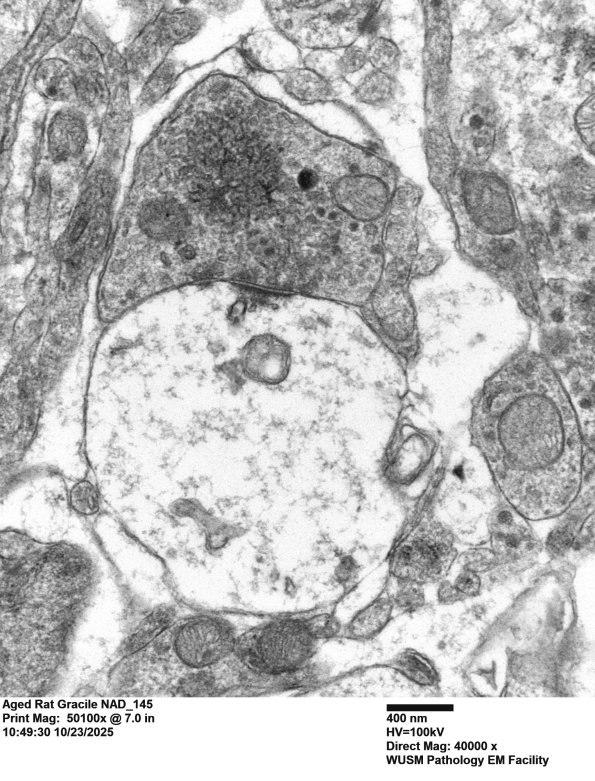

This synapse has a small presynaptic element containing tubulovesicular elements. (electron micrograph)